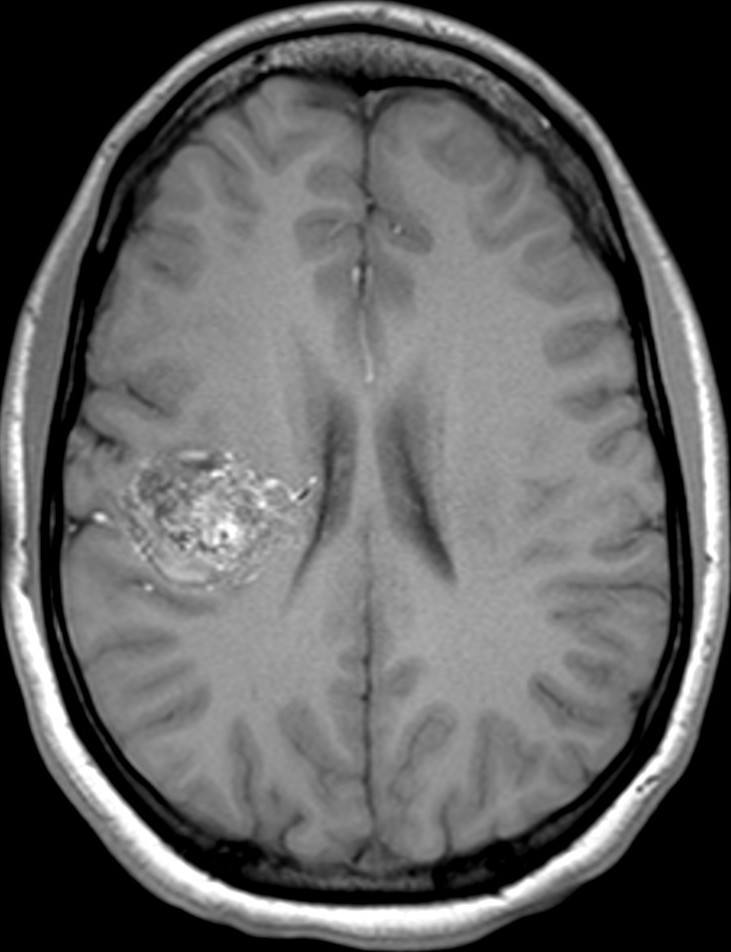

An arteriovenous malformation (AVM) is a tangle of abnormal blood vessels connecting arteries and veins in the brain. AVMs are a rare disease (approximately 1-5 out of 10,000 patients) of the blood vessels in the brain.

In patients with brain AVMs, these connections are incorrect, and arteries in the brain connect directly to veins without the usual interspersed capillaries. This means that high-pressure blood ends up in veins, which are not built to withstand this pressure for a long time. In addition, the arteries usually are abnormally enlarged and tortuous, which is called the ’nidus’ of the AVM.

Most AVMs at some point in the patient’s life become symptomatic. The most common symptoms are headaches, seizures, and bleeding in the brain due to AVM rupture. Less commonly, patients can also present with stroke-like symptoms that are possibly related to the AVM drawing away blood from adjacent normal brain. These symptoms often result in patients undergoing imaging of the brain with a CT or an MRI scan. Alternatively, we sometimes find AVMs ‘incidentally’, for example after a patient suffers from minor head trauma and a CT or MRI is obtained that then shows the AVM.